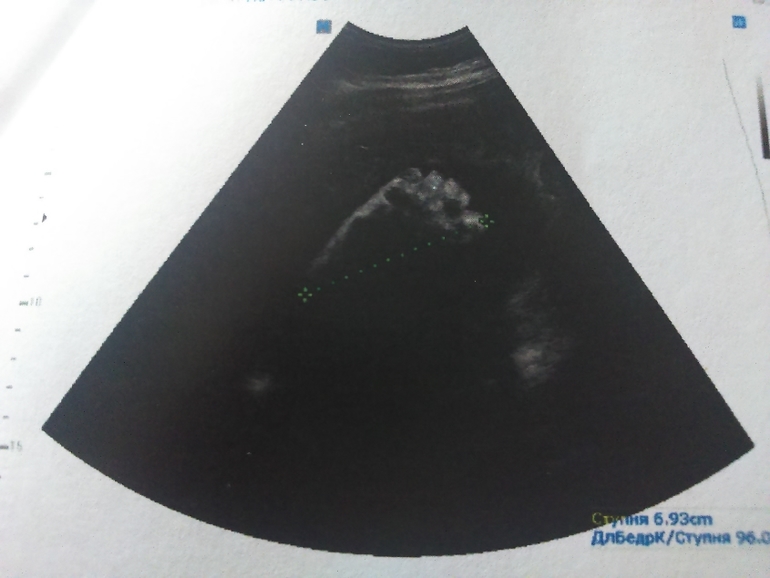

То, что Сынок демонтрирует с удовольствием)))

стопочка